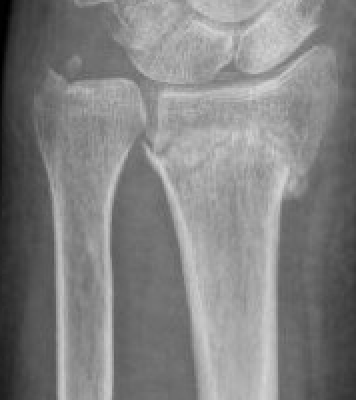

Classification ulna styloid fractures

| Type 1: Tip | Type 2: Base | Type 3: Proximal to styloid |

- RCT of 40 patients with distal radial fractures and base of ulna styloid fractures

- no instabililty, fixation v no fixation of ulna styloid process